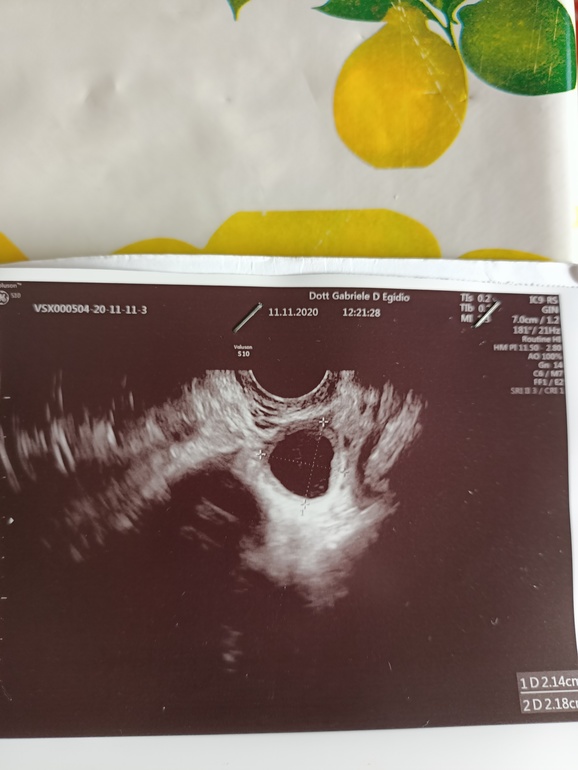

Девчонки кто разбирается что это жт или овула ,просто по ощущениям и по бт овула была раньше,а доктор говорит что овула на 15 ДЦ а я ее чувствовала раньше и вот думаю не мог ошибиться с жт врач?

Фолик с ровным контуром, а здесь на свежую овульку похоже, контур не ровный.

Ну вот и сказал он что овула за день случилась и ещё полное,так что этот цикл тогда можно пропустить и забыть и не ждать ничего

У меня тоже так было жт прям свеженькое, а овуляция была 3 дня назад. Доктор говорит что видит, а как на самом деле только Богу известно

По фото можно предположить, что овуляция была недавно, ЖТ ещё не совсем сформировано, его лучше всего видно на 5дпо и дальше. Но тут можно рассмотреть окантовку фолликула (оно взято в кольцо как бы) и то, что края немного неровные, поэтому думаю ЖТ.

На фоллик похоже. У жт эхогенность другая и на цветочек похоже. Загуглите и сравните по изображениям найденным в гугле. Я за фоллик. И по форме и по эхогенности